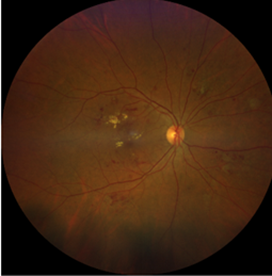

Фото 2. Непролиферативная ДР

При сахарном диабете высокий уровень сахара в крови повреждает мелкие кровеносные сосуды сетчатки. Может возникнуть закупорка сосудов или их повышенная проницаемость. Диабетическая ретинопатия (ДР) подразделяется на непролиферативную диабетическую ретинопатию (НПДР) и пролиферативную диабетическую ретинопатию (ПДР). Такая классификация основана на повреждении кровеносных сосудов сетчатки и появлении новых кровеносных сосудов вне сетчатки и является основой для своевременной диагностики и лечения.

Непролиферативная диабетическая ретинопатия далее подразделяется по степени тяжести на 3 вида: легкая, средняя и тяжелая. При легкой и средней формах отмечаются расширение и выпячивание кровеносных сосудов (микроаневризмы), кровоизлияния внутри сетчатки (интраретинальные кровоизлияния), а также отложение присутствующих в крови компонентов (липопротеинов).

При тяжелой форме к вышеперечисленным изменениям добавляется расширение вен в сетчатке и соединяющие сосуды между венами и артериями (IRMA). Вышеописанные изменения могут наблюдаться в глазном дне в большом количестве.